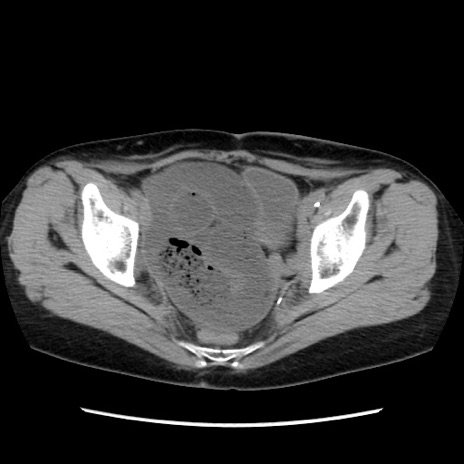

症例32(横断像)

【症例】40歳代 女性

【主訴】上腹部痛、嘔気・嘔吐

【現病歴】約9時間前頃から急に上腹部痛、嘔気、嘔吐が出現。改善しないため救急要請。

【既往歴】子宮頚癌(広汎子宮全摘術、放射線療法)、腸閉塞

【身体所見】腹部:平坦、軟、腸雑音亢進、上腹部を中心に腹部全体に圧痛あり。

【データ】WBC 8400、CRP 0.03